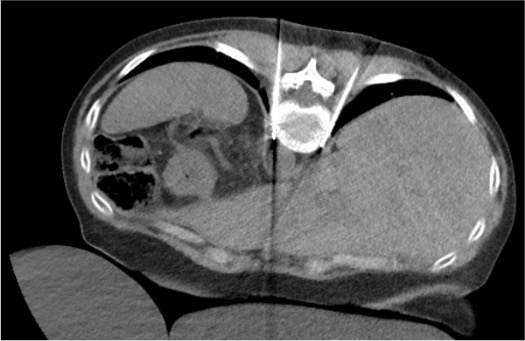

Imaging Review

- CT chest and abdomen: identify T11–T12 paravertebral space, rib heads, pleural reflection, proximal lung parenchyma

- Plan bilateral posterolateral approach to T11–T12 paravertebral fat anterior to vertebral body

- Identify diaphragmatic attachment level — target is at or just above the diaphragmatic crus

- Assess for pleural adhesions, effusions, or prior pneumothorax (relative contraindication)